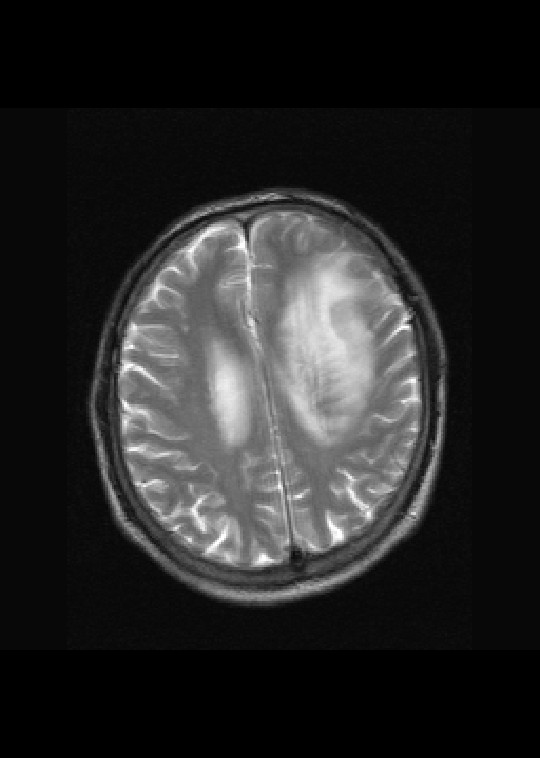

左侧基底节区病灶t1wi呈不均匀稍低信号,t2wi呈稍高信号,周围伴有水肿。增强扫描呈均匀团块样或者抱拳样明显强化,相邻的柔脑膜亦见线样强化。首先考虑淋巴瘤。可惜没有ct平扫,如果ct平扫病灶呈高密度,那么更支持pcnsl的诊断。

左侧基底节区长t1长t2异常团块状信号,增强呈明显均一强化,水肿明显,挤压侧脑室前脚,本人考虑为胶质瘤可能性大。

左侧基底节区病灶t1wi呈不均匀稍低信号,t2wi呈稍高信号,周围伴有水肿。增强扫描呈均匀团块样或者抱拳样明显强化,首先考虑淋巴瘤。

淋巴瘤,信号及强化方式较典型。灶周方广泛水肿相对较少见。长见识了。